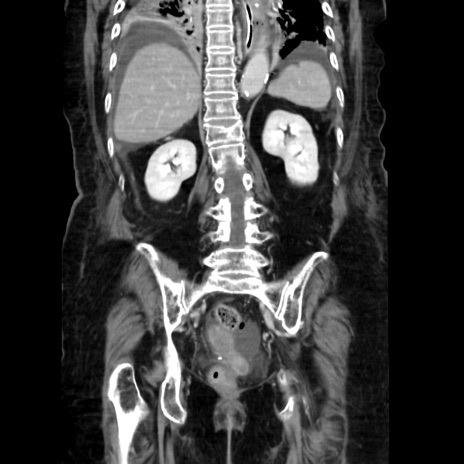

症例40(冠状断像)

冠状断像